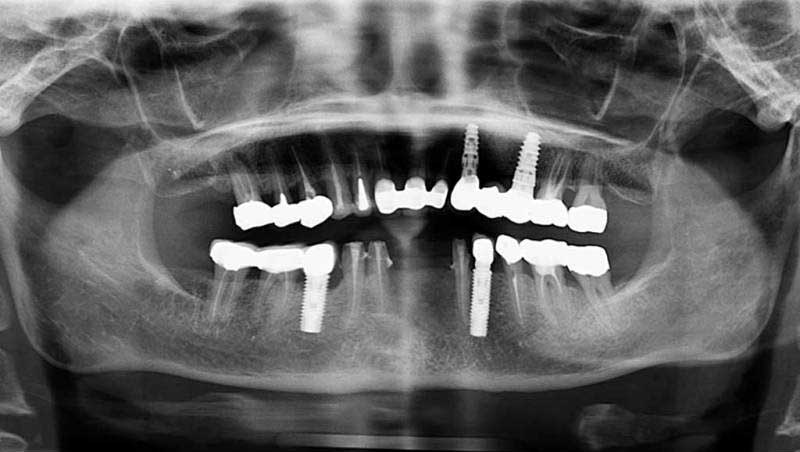

案例1

植牙併發症處理後